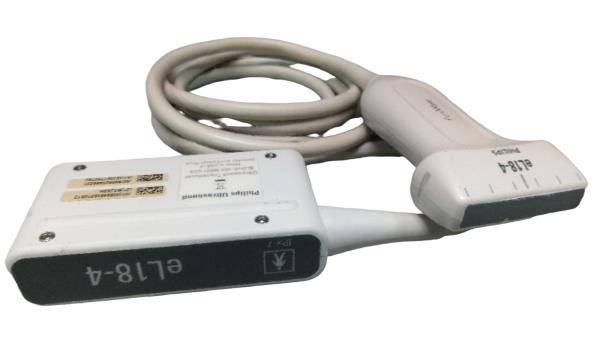

Optional: 3.5MHz R60 convex probe

7.5MHz linear probe: 6.5MHz Trans-vaginal probe

5.0MHz Micro-convex probe: Video Printer Sony UP-897

Probe frequency: Probe frequency